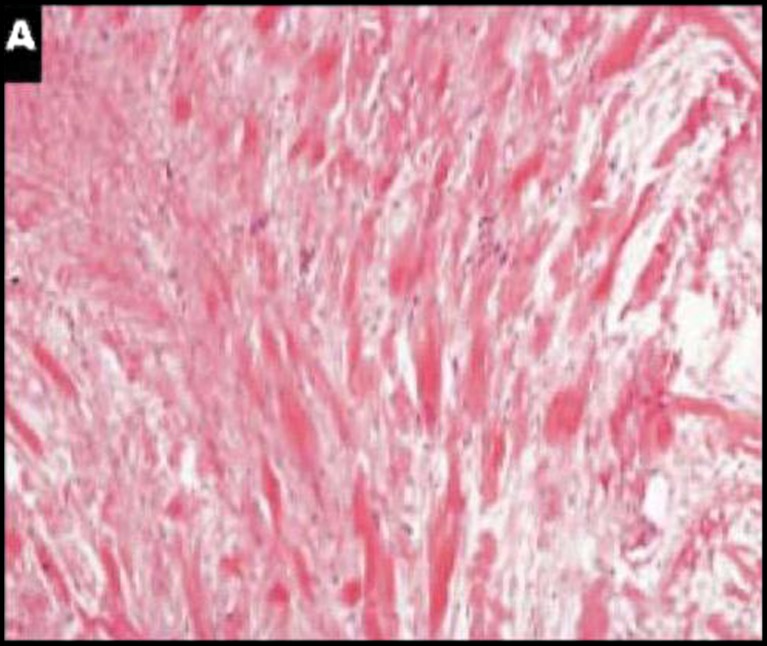

Fig. 1.

a Mesenteric fibromatosis (MF). Note the homogeneous and low-density cellularity and thin-walled, dilated veins (H&E, ×100). b High-power view of a field displaying cytologic characteristics of MF, with stellate fibroblasts, plump nuclei, and micronucleoli (H&E, ×400)